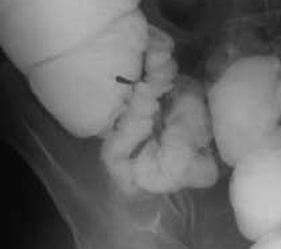

Anse de l'intestin :

Espace inter-anse ne depasse pas 3mm et sa

largeur est 25mm |

Pres de valve Ileo-ceacale , intestin grele

se diminue sa diametre et est moindre des plies

muqueuse que des anses de petit intestin |